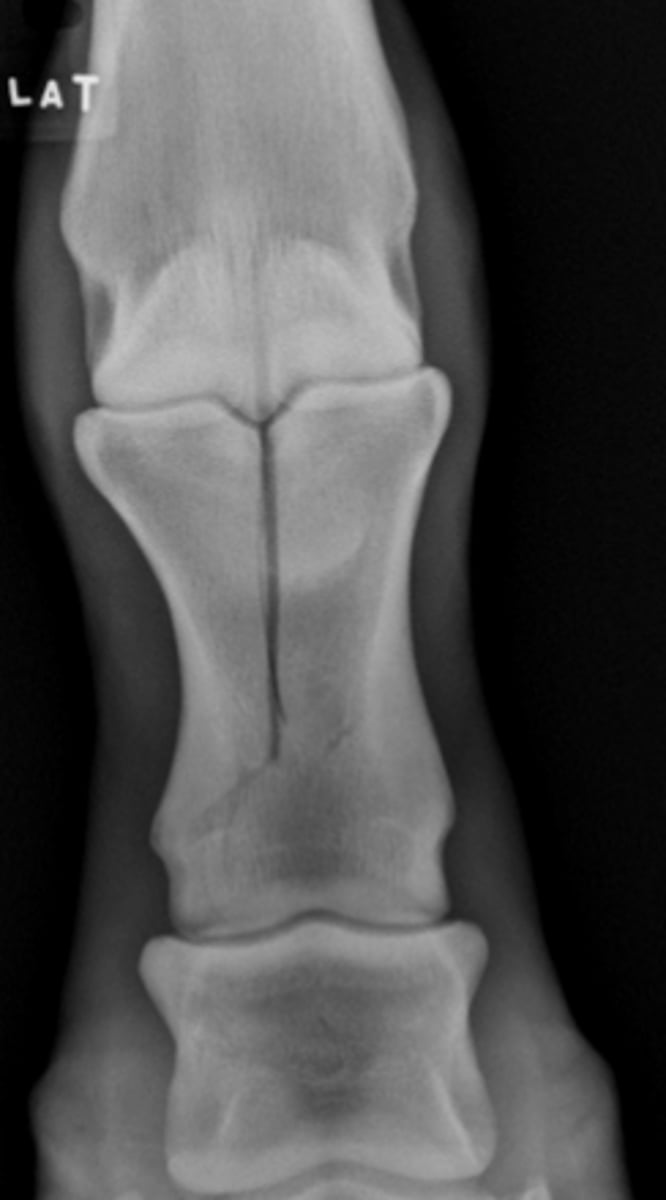

Osteochondral fragment

What is the radiology term for this lesion?

Arthroscopy

What is the preferred treatment for this lesion?